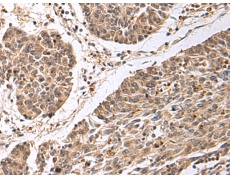

IHC positive control: |

Human colorectal cancer |

IHC Recommend dilution: |

50-100 |